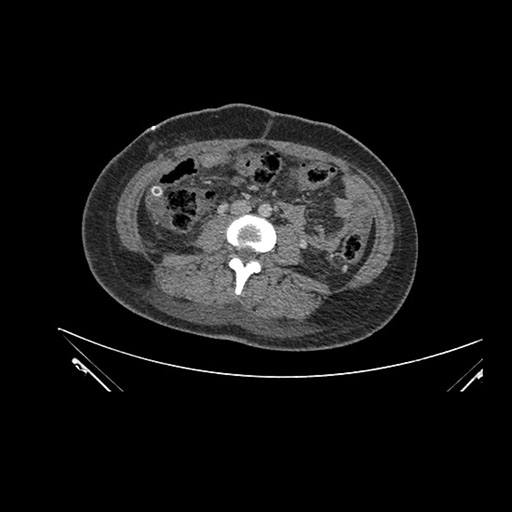

Axial Venous

Coronal Venous